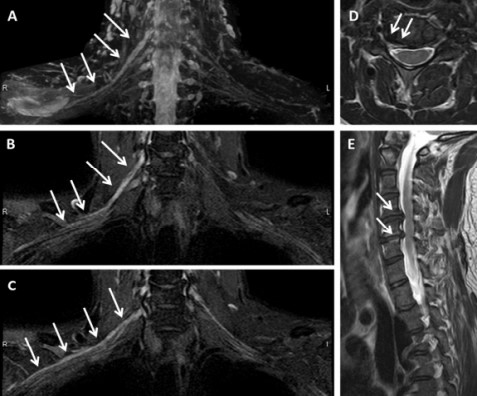

Figure1. Axial CT scanning, locating the upper edge of the facet joint process as the puncture target; After puncture along the predetermined route, inject 10ml ozone; 10ml normal saline and 1ml contrast agent were injected again to show the distribution of contrast agent; After operation, ozone was well distributed in the spinal canal and around the spinal nerve root.